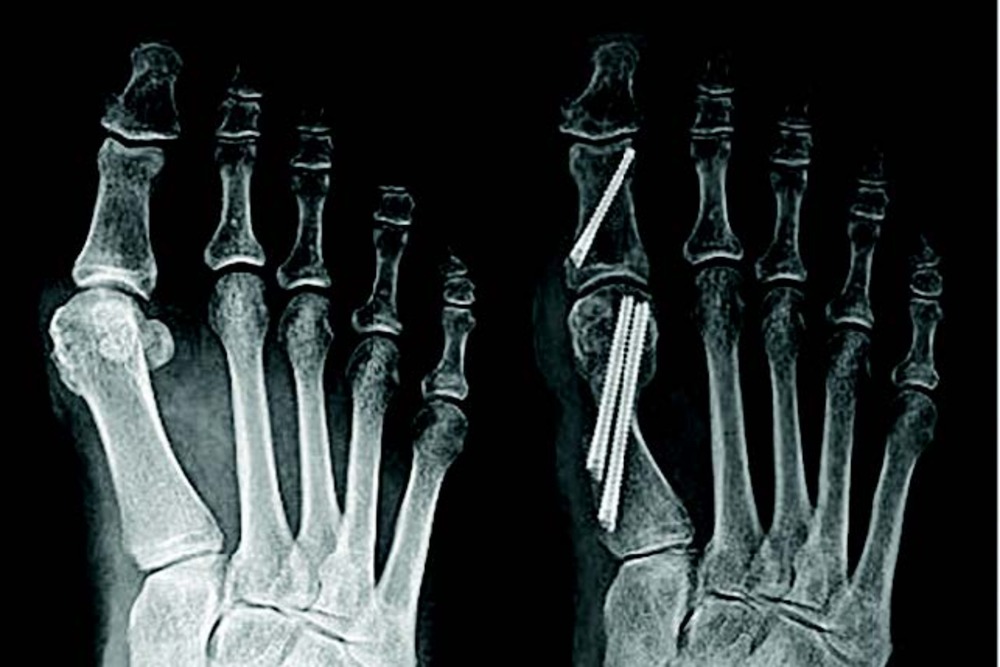

• Forefoot Surgery: Percutaneous bunion correction, hammertoe repair, and metatarsal osteotomies can be performed through tiny stab incisions. These procedures often result in reduced postoperative pain and faster return to activities.

MIS techniques utilize specialized instrumentation and imaging guidance to perform complex procedures through minimal skin incisions, typically ranging from 2-3mm for percutaneous approaches to small incisions under 3cm. Fluoroscopic guidance enables precise bone work and hardware placement without extensive soft tissue dissection.